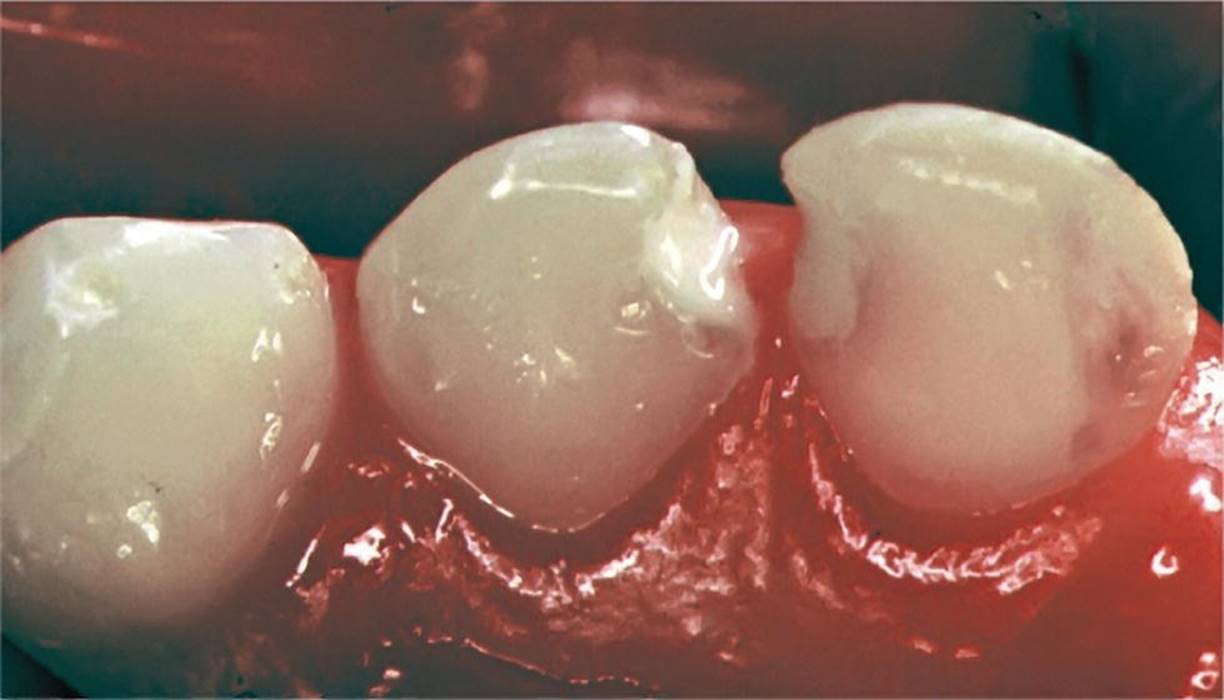

The procedures for applying a rubber dam in two common situations are described in Box 12.6 and illustrated in Figures 12.12 and 12.13. In the first example, the main purpose is to isolate the operation field in the posterior quadrant during the procedures of drilling and filling primary molar teeth (Figure 12.12). The second example is the upper front region where the main objective is to keep the operation field dry (Figure 12.13).

Figure 12.12 Rubber dam for isolating the operation field before restorative therapy of primary molars.